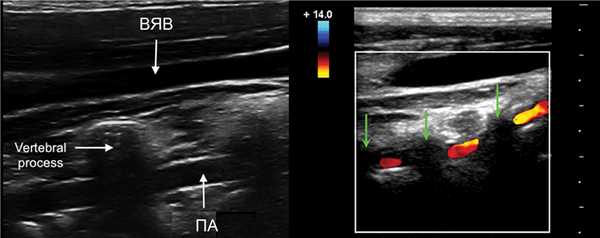

ПА сканируют продольно кнутри от кивательной мышцы, от угла нижней челюсти до верхнего края ключицы.

Для ПА характерна асимметрия, обычно левая больше правой. Когда ПА менее 2 мм, можно говорить о гипоплазии.

Для исследования I сегмента ПА датчик смещают до ключицы. В норме ПА отходит от ПКА на уровне С7 и входит в костный канал на уровне С6.

Возможны варианты, левая ПА отходит от дуги аорты и входит в костный канал на уровне C5.

II сегмент ПА имеет прерывистый вид, т.к. проходит в костном канале поперечных отростков С6-С2 и на месте поперечных отростков акустическое затенение.

Если на смежных участках скорость кровотока примерно одинаковая, значит патологических изменений в «слепой» зоне нет.

Спектр II сегмента ПА по форме похож на ВСА, Vps и Ved в 1,5 раза ниже, поток исключительно антеградный. Vps может снижаться на верхних отрезках, но не более 20%.

ПА обеих сторон имеют одинаковый просвет лишь в 26-44% случаев, часто определяют асимметрию скорости, у здоровых